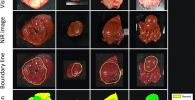

HyperMLPA is an interdisciplinary workshop which aims at bringing together people of different communities and disciplines involved in hyperspectral sensing, machine learning, and pattern analysis. People are invited to contribute in sensor development and calibration, to present and publish new datasets, to present innovative methodological advancements, and to share the latest results and findings of application-oriented work.